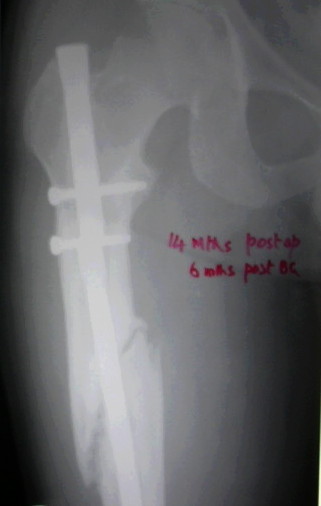

The second picture shows a plain guide wire inserted thro the nail, prograde, hammered out thro the distal femur, out thro the skin. A beaded guide wire being railroaded on the earlier G W into the distal end of the nail.

Dr Eid, you may also appreciate these.

This picture shows the beaded guide wire into the nail from its distal end.

V M Iyer